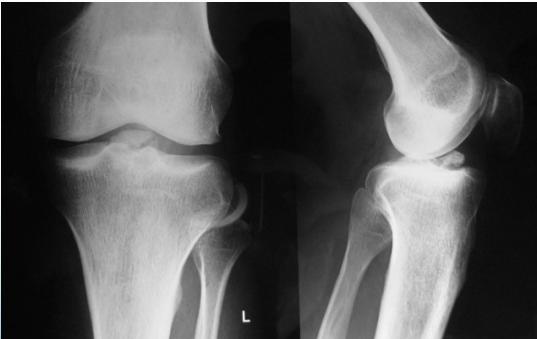

Plain X-ray

- Excludes other bony injuries

- Identifies tibial eminence fracture (signifies ACL bony avulsion)